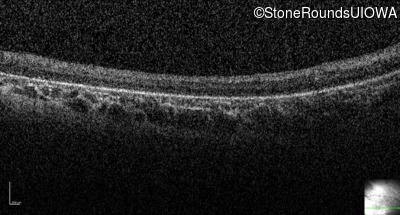

Optical Coherence Tomography - Right - Light Perception

Exemplar

Optical Coherence Tomography - Left - Light Perception